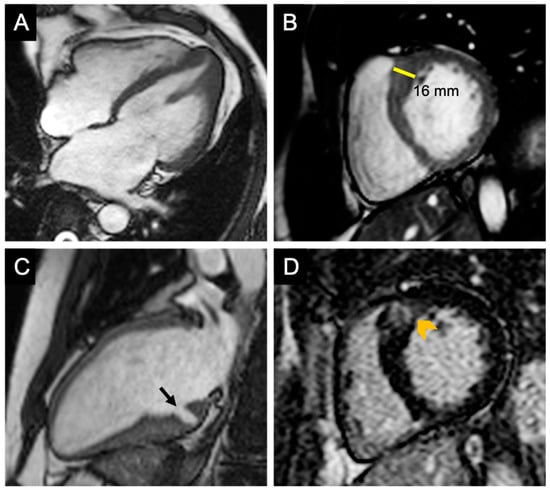

Short-axis cine images are useful for measuring LV wall thickness, volumes, and LVEF. Because of its high contrast between the myocardium and blood pool, CMR permits an accurate measurement of the segments poorly visible with echocardiography such as the basal anterior segment and the apical segments (Figure 3A,B). Most frequently, hypertrophy is localized at the level of the contiguity of the basal antero-septal wall with the basal anterior wall [153] (Figure 3B).

CMR is able to identify myocardial crypts, defined as invaginations that penetrate more than 50% of the compact myocardium at end-diastole and collapse at end-systole [150] (Figure 3C). Usually, they are multiple and located in the basal inferior LV wall. Myocardial crypts may be also encountered in the healthy population; however [149], they are more prevalent in patients with genotype-positive HCM, with and without hypertrophy [150].

Another imaging biomarker that is easily identified with CMR in patients with HCM is the apical-to-basal muscle band. This unique structure was detected in 60% of phenotype-positive HCM patients as well as in genotype-positive, phenotype-negative family members [148].

Anomalies of the mitral valve apparatus may also be assessed by CMR. Apical insertion and other conformational anomalies of papillary muscles, as well as elongation of the anterior mitral valve, may be subtle findings encountered in genotype-positive, even in pre-hypertrophic, stages (Figure 3A).

The addition of gadolinium-based contrast agents (GBCA) permits the detection and quantification of myocardial fibrosis. Two different types of myocardial fibrosis may be encountered in the setting of HCM: replacement fibrosis (scar), which appears to be linked to periods of ischemia and cardiomyocyte necrosis; this type of fibrosis can be detected on LGE sequences (Figure 3D); and interstitial fibrosis—a reactive, diffuse process identifiable by T1 mapping techniques; the measurement of T1 relaxation times before and after GBCA administration is able to estimate the extracellular volume fraction (ECV) [154].